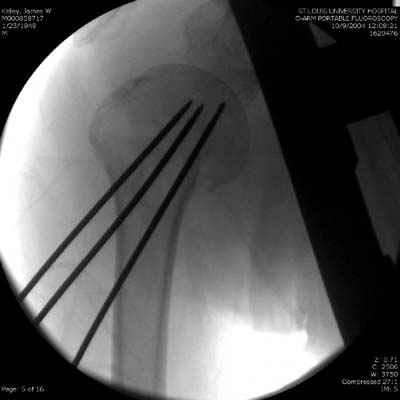

Пока я пользуюсь методикой принятой у нас (методика Сиэтла), также перкутанный спицевой метод, только сцицы 2.8 мм с резбой на конце.

Здесь случай перелома-вывиха плеча, больному 56 лет, после "дважды" закрытой неудачной репозиции, опять же ургентно взяли в операционную, после полного общего обезболивания попытались сделать репозицию, и фиксацию провели спицами.

Больной находился в повязке, примерно напоминяющей косыночную, рекомендованы движения в локтевом суставе и маятниковые движения в плече, спицы удалены в три недели (были случаи миграции)

Больной амбулаторный, предупрежден на случай осложнения АВН головки.